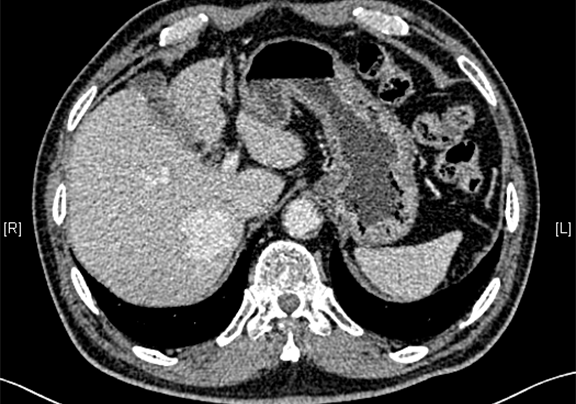

术前CT检查:

动脉期

静脉期

平衡期